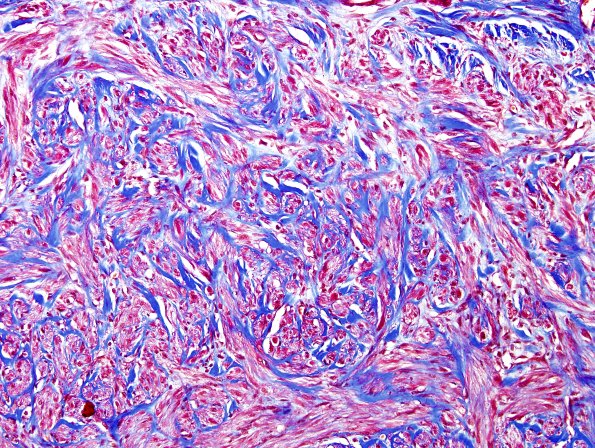

8C2 Neuroma (Case 8) Trichrome 1

Collagenous stroma involves both haphazard elements to mini-fascicles. (Trichrome)